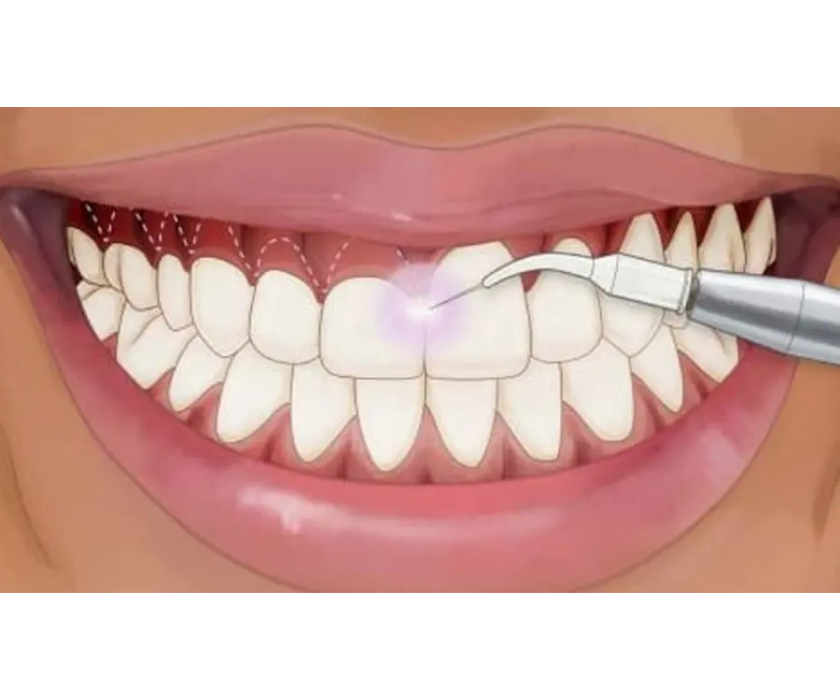

Đây là phương pháp đơn giản và phổ biến nhất, áp dụng cho những trường hợp hở lợi nhẹ do nướu phát triển che phủ thân răng. Bác sĩ sẽ dùng laser hoặc dao phẫu thuật để cắt bỏ phần lợi thừa, bộc lộ răng nhiều hơn, giúp nụ cười cân đối. Chi phí điều trị thường thấp, thời gian hồi phục nhanh và ít gây khó chịu.

Đặc biệt, An Trí hiện đang ứng dụng công nghệ laser trong điều trị cười hở lợi, giúp rút ngắn đáng kể thời gian phẫu thuật, hạn chế chảy máu, giảm sưng đau sau thủ thuật và mang lại kết quả thẩm mỹ tự nhiên. Đây cũng là lựa chọn tiết kiệm chi phí, phù hợp với nhiều bệnh nhân mong muốn cải thiện nụ cười nhưng vẫn đảm bảo an toàn và hiệu quả lâu dài.

Nha khoa An Trí cắt nướu bằng laser an toàn hạn chế chảy máu

Nha khoa An Trí cắt nướu bằng laser an toàn hạn chế chảy máu